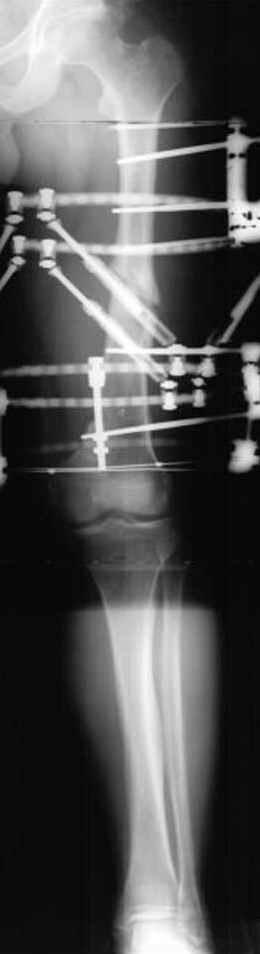

Отправитель: Djoldas Kuldjanov 23 Ноябрь 2004, 18:21

пластическая модель; и коррекция бедра аппаратом Илизарова.

Имею другие снимки тоже, получится как отчет о моей работе.

хотя даже если бы и инфекция , то nail exchange с рассверливанием канала - вариант дебрайдмента) Я думаю, что последовательность развития событий:

Узкий к-м канал - тонкий гвоздь- усталостный перелом дистальных винтов - развитие нестабильности и как ее результат остеолиз вокруг гвоздя - деформация анатомической оси бедра. Похоже, что я понял почему аппарат, а не новый гвоздь:-)